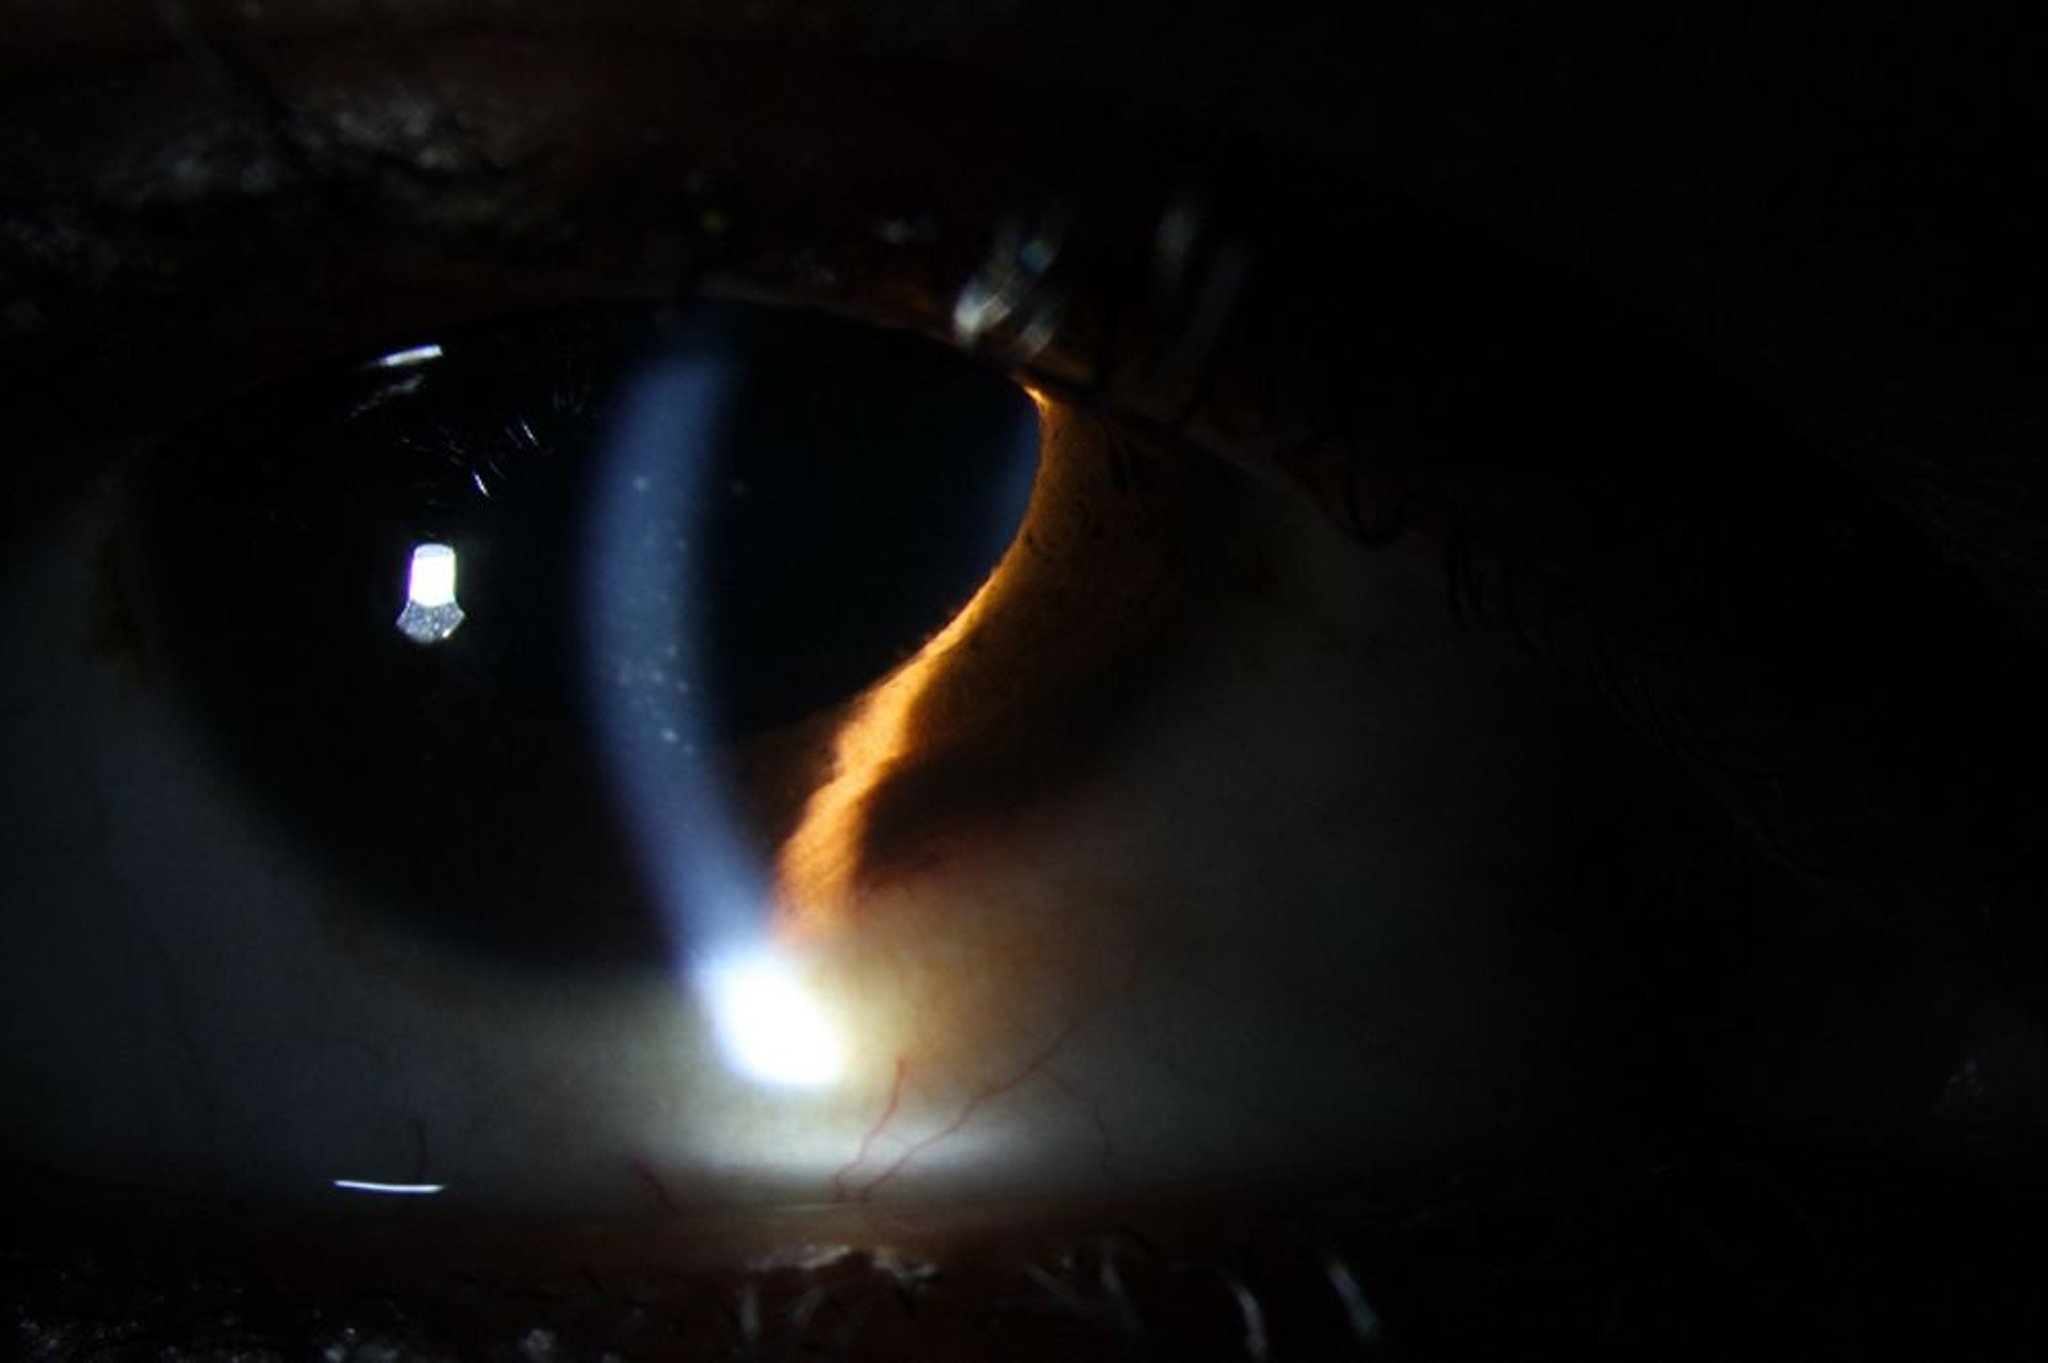

Viêm màng bồ đào trước có thể gây đỏ, chất kết tủa viêm giác mạc trên nội mô giác mạc (hình minh họa), cũng như các bạch cầu và đốm sáng (protein) ở tiền phòng.

Hình ảnh do bác sĩ Sunir Garg cung cấp.